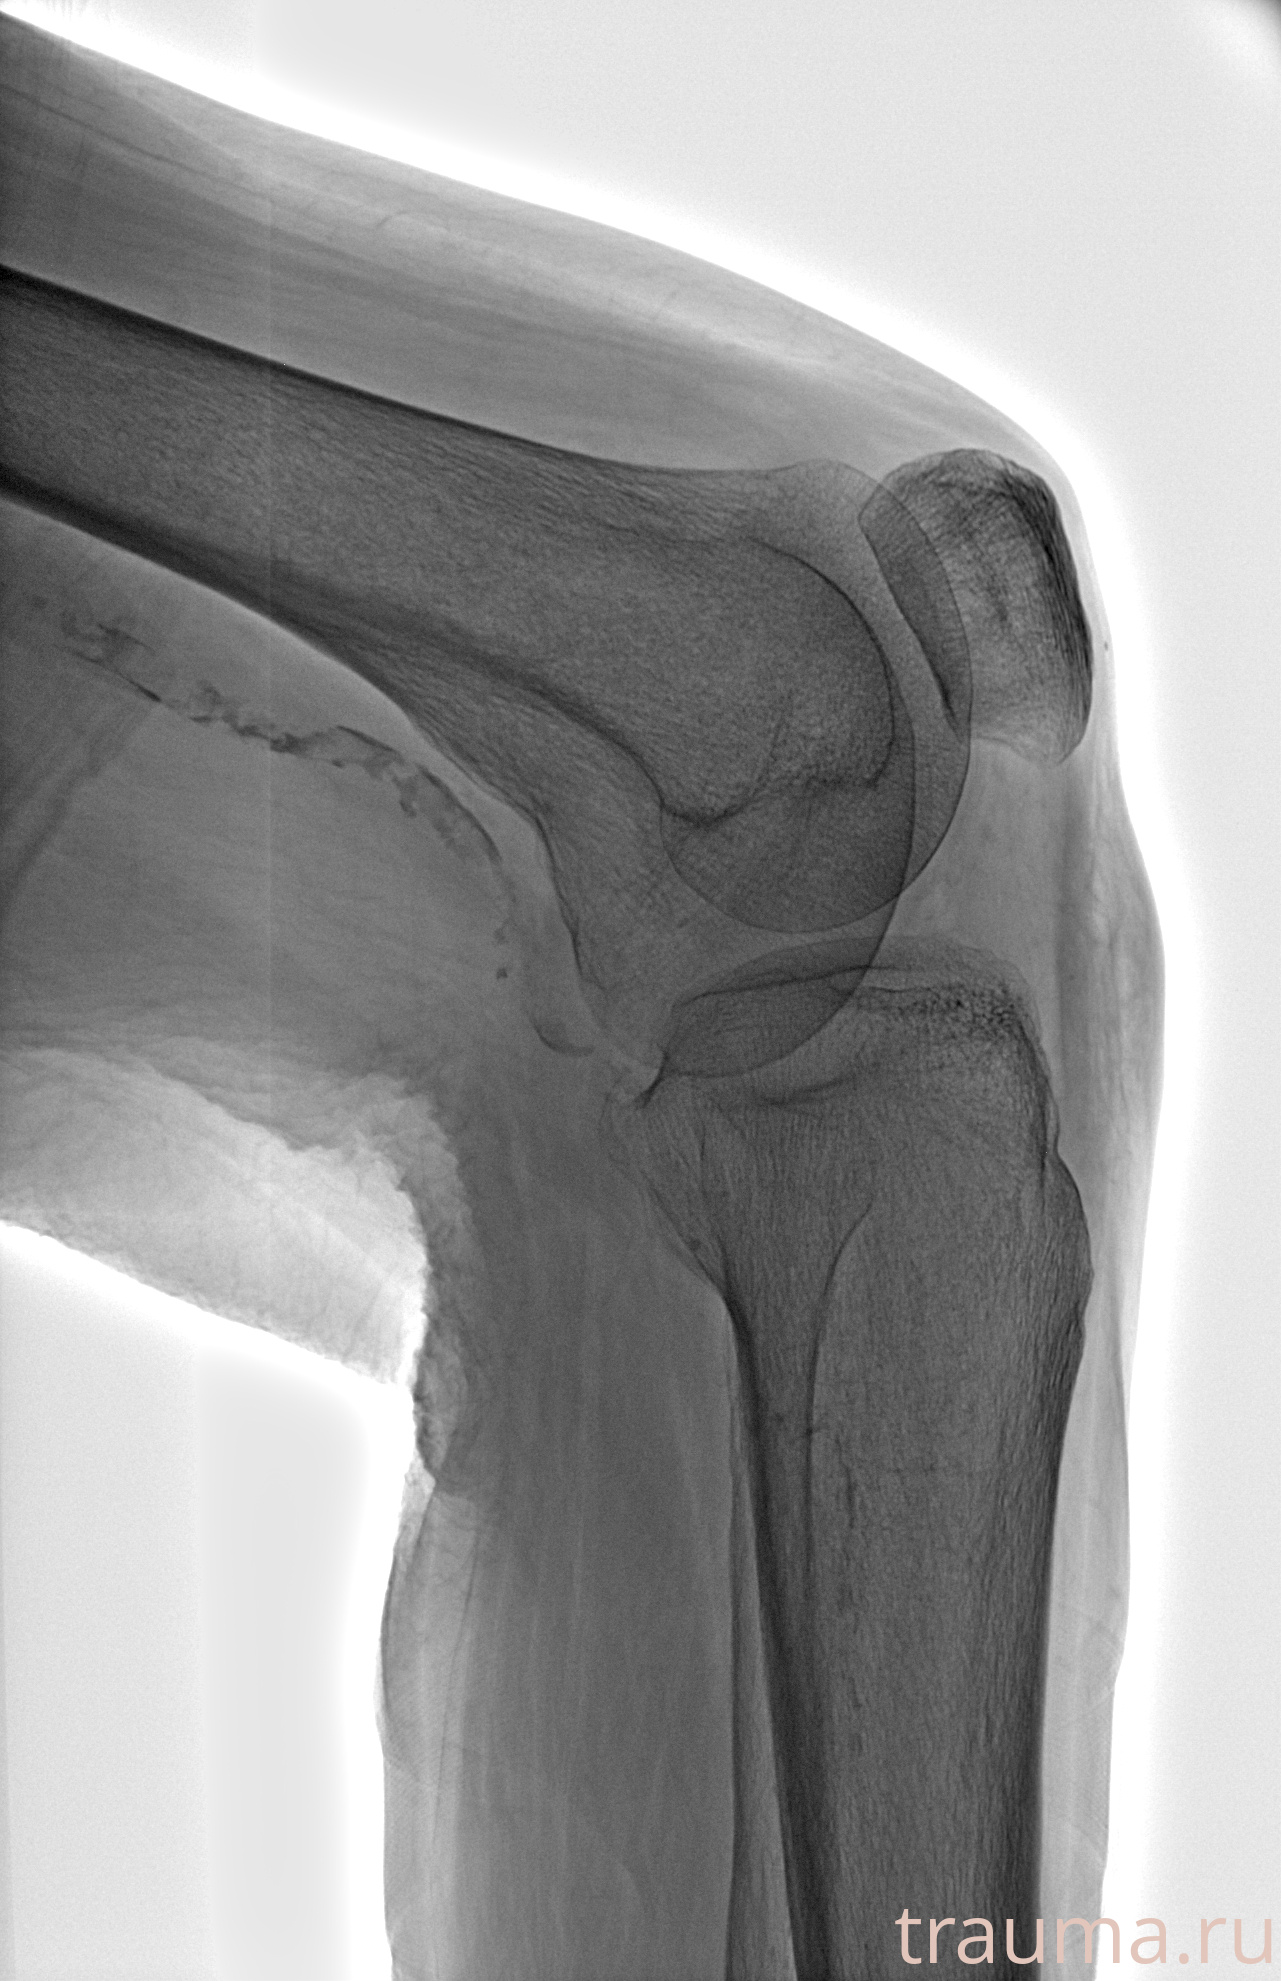

Рентгенограммы

Рентген на дому: по вашему адресу приезжает врач-рентгенолог, травматолог-ортопед с мобильным рентгеновским аппаратом, проводит диагностику травмы или заболевания, делает необходимые рентгенограммы, дает рекомендации по дальнейшему лечению. Получить качественные снимки в домашних условиях возможно благодаря уникальной методике, разработанной МосРентген Центром для института  Склифосовского